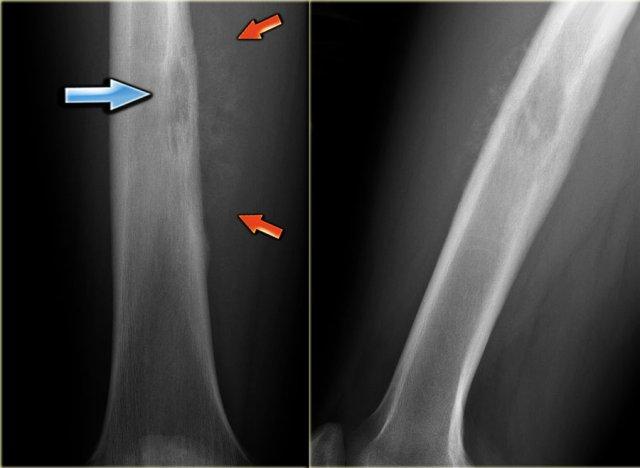

Ewing’s sarcoma in diaphysis of the femur. Notice ill-defined zone of transition (blue arrow) and aggressive type of periosteal reaction (red arrows)

Bên trái là hình ảnh bệnh nhân có u xương Ewing ở xương đùi.

Lưu ý vùng tiêu xương không rõ ranh giới.

Có phản ứng màng xương xâm lấn.